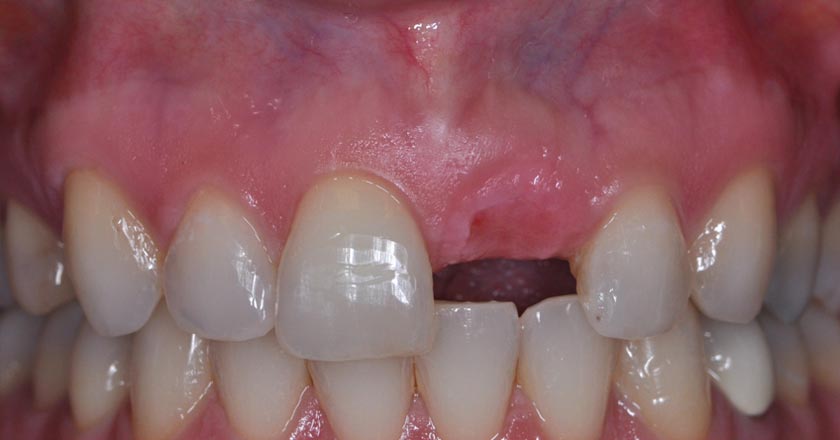

Implant - Before And After

Dental implant – before procedure

Dental implant – after procedure